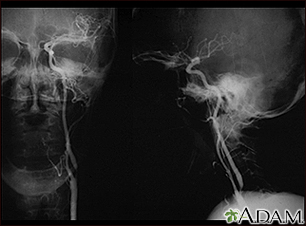

BACK TOTOP Browse A-ZSearchBrowse A-ZABCDEFGHIJKLMNOPQRSTUVWXYZ0-9 E-mail FormEmail ResultsName:Email address:Recipients Name:Recipients address:Message: Print-FriendlyBookmarksbookmarks-menuStrokeCerebrovascular disease; CVA; Cerebral infarction; Cerebral hemorrhage; Ischemic stroke; Stroke - ischemic; Cerebrovascular accident; Stroke - hemorrhagic; Carotid artery - strokeA stroke occurs when blood flow to a part of the brain stops. A stroke is sometimes called a "brain attack." If blood flow is cut off for longer than a few seconds, the brain cannot get nutrients and oxygen. Brain cells can die, causing lasting damage.A stroke can also occur if a blood vessel inside the brain bursts, leading to bleeding inside the head.Related video goes here for no-HTML5 browsers Causes There are two major types of stroke: Ischemic stroke Hemorrhagic stroke Ischemic stroke occurs when a blood vessel that supplies blood to the brain is blocked by a blood clot. This may happen in two ways: A clot may form in an artery that is already very narrow. This is called a thrombotic stroke. A clot may break off from another place in the blood vessels of the brain, or from some other part of the body, and travel up to the brain. This is called cerebral embolism, or an embolic stroke. Ischemic strokes may also be caused by a sticky substance called plaque that can clog arteries.No audio descriptionWith audio descriptionRelated video goes here for no-HTML5 browsersRelated video goes here for no-HTML5 browsersA hemorrhagic stroke occurs when a blood vessel in part of the brain becomes weak and bursts open. This causes blood to leak into the brain. Some people have defects in the blood vessels of the brain that make this more likely. These defects may include: Aneurysm (weak area in the wall of a blood vessel that causes the blood vessel to bulge or balloon out) AneurysmAn aneurysm is a weak area in the wall of a blood vessel that causes the blood vessel to bulge or balloon out. When an aneurysm occurs in a blood ve...ImageRead Article Now Book Mark Article Arteriovenous malformation (AVM; abnormal connection between the arteries and veins) Arteriovenous malformationA cerebral arteriovenous malformation (AVM) is an abnormal connection between the arteries and veins in the brain that usually forms before birth....ImageRead Article Now Book Mark Article Cerebral amyloid angiopathy (CAA; condition in which proteins called amyloid build up on the walls of the arteries in the brain) Cerebral amyloid angiopathyCerebral amyloid angiopathy (CAA) is a condition in which proteins called amyloid build up on the walls of the arteries in the brain. CAA causes ble...ImageRead Article Now Book Mark Article Hemorrhagic strokes may also occur when someone is taking blood thinners, such as dabigatran, rivaroxaban, apixaban, edoxaban and warfarin or has a bleeding disorder. Very high blood pressure may cause blood vessels to burst, leading to hemorrhagic stroke. An ischemic stroke can develop bleeding and become a hemorrhagic stroke.High blood pressure is the main risk factor for strokes. Other major risk factors are:High blood pressureBlood pressure is a measurement of the force exerted against the walls of your arteries as your heart pumps blood to your body. Hypertension is the ...ImageRead Article Now Book Mark Article Risk factor for strokesA stroke occurs when blood flow to a part of the brain suddenly stops. A stroke is sometimes called a brain attack or cerebrovascular accident (CVA)...ImageRead Article Now Book Mark Article Irregular heartbeat, called atrial fibrillation Atrial fibrillationAtrial fibrillation (AFib) and atrial flutter are common types of abnormal heart rhythms (arrhythmias) which affect the upper chambers (atria) of the...ImageRead Article Now Book Mark Article Diabetes DiabetesDiabetes is a long-term (chronic) disease in which the body cannot regulate the amount of sugar in the blood.ImageRead Article Now Book Mark Article Smoking Family history of stroke Being male High cholesterol High cholesterolCholesterol is a fat (also called a lipid) that your body needs to work properly. Too much bad cholesterol in your blood can increase your chance of...ImageRead Article Now Book Mark Article Increasing age, especially after age 55 Ethnicity (African Americans are more likely to die of a stroke) Obesity History of prior stroke or transient ischemic attack (occurs when blood flow to a part of the brain stops for a brief time) Transient ischemic attackA transient ischemic attack (TIA) occurs when blood flow to a part of the brain stops for a brief time. A person will have stroke-like symptoms for ...ImageRead Article Now Book Mark Article Related video goes here for no-HTML5 browsersStroke risk is also higher in: People who have heart disease or poor blood flow in their legs caused by narrowed arteries Poor blood flow in their legsPeripheral artery disease (PAD) is a condition of the blood vessels that supply the legs and feet. It occurs due to narrowing of the arteries in the...ImageRead Article Now Book Mark Article People who have unhealthy lifestyle habits such as excessive use of alcohol, use of recreational drugs, a high-fat diet, or lack of exercise Unhealthy lifestyleGood health habits can allow you to avoid illness and improve your quality of life. The following steps will help you feel better and live better. G...ImageRead Article Now Book Mark Article People who have a hereditary tendency to develop blood clots Women who take birth control pills (especially those who smoke and are older than 35) Women who are pregnant Women who take hormone replacement therapy Patent foramen ovale (PFO), a hole between the left and right atria (upper chambers) of the heart Patent foramen ovale (PFO)Patent foramen ovale (PFO) is a hole between the left and right atria (upper chambers) of the heart. This hole exists in everyone before birth, but ...ImageRead Article Now Book Mark Article People who have sleep disorders (such as obstructive sleep apnea)Obstructive sleep apneaObstructive sleep apnea (OSA) is a problem in which your breathing pauses during sleep. This occurs because of narrowed or blocked airways.ImageRead Article Now Book Mark Article Symptoms Symptoms of stroke depend on which part of the brain is damaged. In some cases, a person may not know that a stroke has occurred. Most of the time, symptoms develop suddenly and without warning. But symptoms may occur on and off for the first day or two. Symptoms are usually most severe when the stroke first happens, but they may slowly get worse.Previous imagePlay SlideshowStop SlideshowNext image / A headache may occur if the stroke is caused by bleeding in the brain. The headache: Starts suddenly and may be severe May be worse when you are lying flat May wake you up from sleep May get worse when you change positions or when you bend, strain, or cough Previous imagePlay SlideshowStop SlideshowNext image / Other symptoms depend on how severe the stroke is, and what part of the brain is affected. Symptoms may include:Change in alertness (including sleepiness, unconsciousness, and coma) Change in alertnessDecreased alertness is a state of reduced awareness and is often a serious condition. A coma is the most severe state of decreased alertness in which...Read Article Now Book Mark Article Changes in hearing or taste Changes that affect touch and the ability to feel pain, pressure, or different temperatures Confusion or loss of memory ConfusionConfusion is the inability to think as clearly or quickly as you normally do. You may feel disoriented and have difficulty paying attention, remembe...ImageRead Article Now Book Mark Article Problems swallowing Problems swallowingDifficulty with swallowing is the feeling that food or liquid is stuck in the throat or at any point before the food enters the stomach. This proble...ImageRead Article Now Book Mark Article Problems writing or reading Dizziness or abnormal feeling of movement (vertigo) DizzinessDizziness is a term that is often used to describe 2 different symptoms: lightheadedness and vertigo. Lightheadedness is a feeling that you might fai...ImageRead Article Now Book Mark Article Eyesight problems, such as decreased vision, double vision, or total loss of vision Lack of control over the bladder or bowels Loss of balance or coordination, or trouble walking Muscle weakness in the face, arm, or leg (usually just on one side) Numbness or tingling on one side of the body Personality, mood, or emotional changes Trouble speaking or understanding others who are speaking Exams and Tests Your health care provider will do a physical exam to: Check for problems with vision, movement, feeling, reflexes, understanding, and speaking. Your provider and nurses will repeat this exam over time to see if your stroke is getting worse or improving. Listen to the carotid arteries in the neck with a stethoscope for an abnormal sound, called a bruit, which is caused by abnormal blood flow. Check for high blood pressure and an irregular heartbeat. Previous imagePlay SlideshowStop SlideshowNext image / You may have the following tests to help find the type, location, and cause of the stroke and check for other problems:CT scan or MRI scan of the brain to determine the location of the stroke, and if there is a mass, or any bleeding CT scanA head computed tomography (CT) scan uses many x-rays to create pictures of the head, including the skull, brain, eye sockets, and sinuses.ImageRead Article Now Book Mark Article MRI scanA head MRI (magnetic resonance imaging) is an imaging test that uses powerful magnets and radio waves to create pictures of the brain and surrounding...ImageRead Article Now Book Mark Article Angiogram of the head to look for a blood vessel that is blocked or bleeding Angiogram of the headCerebral angiography is a procedure that uses a special dye (contrast material) and x-rays to see how blood flows through the brain.ImageRead Article Now Book Mark Article Carotid duplex (ultrasound) to see if the carotid arteries in your neck have narrowed Carotid duplexCarotid duplex is an ultrasound test that shows how well blood is flowing through the carotid arteries. The carotid arteries are located in the neck...ImageRead Article Now Book Mark Article Echocardiogram to see if the stroke could have been caused by a blood clot from the heart EchocardiogramAn echocardiogram is a test that uses sound waves to create pictures of the heart. The picture and information it produces is more detailed than a s...ImageRead Article Now Book Mark Article Magnetic resonance angiography (MRA) or CT angiography to check for abnormal blood vessels in the brain Magnetic resonance angiographyMagnetic resonance angiography (MRA) is an MRI exam of the blood vessels. Unlike traditional angiography that involves placing a tube (catheter) int...ImageRead Article Now Book Mark Article Other tests include: Blood tests Electroencephalogram (EEG) to determine if there are seizures ElectroencephalogramAn electroencephalogram (EEG) is a test to measure the electrical activity of the brain.ImageRead Article Now Book Mark Article Electrocardiogram (ECG) and heart rhythm monitoringElectrocardiogramAn electrocardiogram (ECG) is a test that records the electrical activity of the heart.ImageRead Article Now Book Mark Article Heart rhythm monitoringA Holter monitor is a machine that continuously records the heart's rhythms. The monitor is worn for 24 to 48 hours during normal activity.ImageRead Article Now Book Mark Article Treatment A stroke is a medical emergency. Quick treatment is needed. Call 911 or the local emergency number right away or seek urgent medical care at the first signs of a stroke. People who are having stroke symptoms need to get to a hospital as quickly as possible. If the stroke is caused by a blood clot, a clot-busting medicine may be given to dissolve the clot (also called thrombolytic therapy). To be effective, this treatment must be started within 4 1/2 hours of when the symptoms first started. However, the sooner this treatment is started, the better the chance of a good outcome. Endovascular thrombectomy may be needed. This is when a catheter is inserted into your arteries. Dye is injected while images of your brain's blood vessels are reviewed. A clot, if found, could be removed through the catheter.Other treatments given in the hospital depend on the cause of the stroke. These may include: Blood thinners such as heparin, warfarin, direct acting oral anticoagulants (DOACs), aspirin, or clopidogrel (Plavix) Medicine to control risk factors for stroke, such as high blood pressure, diabetes, and high cholesterol Special procedures or surgery to relieve symptoms or prevent more strokes Nutrients and fluids Physical therapy, occupational therapy, speech therapy, and swallowing therapy will all begin in the hospital. If the person has severe swallowing problems, a feeding tube in the stomach (gastrostomy tube) will likely be needed.The goal of treatment after a stroke is to help you recover as much function as possible and prevent future strokes. Recovery from your stroke will begin while you are still in the hospital or at a rehab center. It will continue when you go home from the hospital or center. Be sure to follow up with your provider after you go home. RecoveryA stroke happens when blood flow to any part of the brain stops. Each person has a different recovery time and need for long-term care. Problems wit...Read Article Now Book Mark Article Support Groups More information and support for people with stroke and their families can be found on the American Stroke Association website -- www.stroke.org/en/help-and-support. Outlook (Prognosis) How well a person does after a stroke depends on:The type of stroke How much brain tissue is damaged What body functions have been affected How quickly treatment is given Problems moving, thinking, and talking often start to improve in the days to weeks after a stroke.Many people develop depression after a stroke. This can slow down recovery but is also a very treatable complication of a stroke.DepressionDepression may be described as feeling sad, blue, unhappy, miserable, or down in the dumps. Most of us feel this way at one time or another for shor...ImageRead Article Now Book Mark Article Many people who have had a stroke will keep improving in the months or years after their stroke. Over half of people who have a stroke are able to function and live at home. Others are not able to care for themselves.If treatment with clot-busting medicines is successful, the symptoms of a stroke may go away. However, people often do not get to the hospital soon enough to receive these medicines, or they cannot take these medicines because of a health condition.People who have a stroke from a blood clot (ischemic stroke) have a better chance of surviving than those who have a stroke from bleeding in the brain (hemorrhagic stroke).The risk for a second stroke is highest during the weeks or months after the first stroke. The risk begins to decrease after this period. When to Contact a Medical Professional Stroke is a medical emergency that needs to be treated right away. The acronym F.A.S.T. is an easy way to remember signs of stroke and what to do if you think a stroke has occurred. The most important action to take is to call 911 or the local emergency number right away for emergency assistance. F.A.S.T. stands for:FACE. Ask the person to smile. Check if one side of the face droops. ARMS. Ask the person to raise both arms. See if one arm drifts downward. SPEECH. Ask the person to repeat a simple sentence. Check if words are slurred and if the sentence is repeated correctly. TIME. If a person shows any of these symptoms, time is essential. It is important to get to the hospital as quickly as possible. Call 911 or the local emergency number. Act F.A.S.T. Prevention Reducing your stroke risk factors lessens your chance of having a stroke. Risk factorsA stroke occurs when blood flow to a part of the brain suddenly stops. A stroke is sometimes called a brain attack or cerebrovascular accident (CVA)...ImageRead Article Now Book Mark Article Open ReferencesReferencesBiller J, Schneck MJ, Ruland S. Ischemic cerebrovascular disease. In Jankovic J, Mazziotta JC, Pomeroy SL, Newman NJ, eds. Bradley's and Daroff's Neurology in Clinical Practice. 8th ed. Philadelphia, PA: Elsevier; 2022:chap 65.Bushnell C, Kernan WN, Sharrief AZ, et al. 2024 Guideline for the primary prevention of stroke: a guideline from the American Heart Association/American Stroke Association. Stroke. 2024;55(12):e344-e424. PMID: 39429201 pubmed.ncbi.nlm.nih.gov/39429201/.Chaturvedi S, Selim M. Hemorrhagic cerebrovascular disease. In: Goldman L, Cooney KA, eds. Goldman-Cecil Medicine. 27th ed. Philadelphia, PA: Elsevier; 2024:chap 377.Gladstone DJ, Lindsay MP, Douketis J, et al. Canadian stroke consortium. Canadian stroke best practice recommendations: secondary prevention of stroke Update 2020. Can J Neurol Sci. 2022;49(3):315-337. PMID: 34140063 pubmed.ncbi.nlm.nih.gov/34140063/.Goldstein LB. Ischemic cerebrovascular disease. In: Goldman L, Cooney KA, eds. Goldman-Cecil Medicine. 27th ed. Philadelphia, PA: Elsevier; 2024:chap 376.Joglar JA, Chung MK, Armbruster AL, et al. 2023 ACC/AHA/ACCP/HRS Guideline for the diagnosis and management of atrial fibrillation: a report of the American College of Cardiology/American Heart Association Joint Committee on clinical practice guidelines. Circulation. 2024;149(1):e1-e156. PMID: 38033089 pubmed.ncbi.nlm.nih.gov/38033089/.Kleindorfer DO, Towfighi A, Chaturvedi S, et al. 2021 Guideline for the prevention of stroke in patients with stroke and transient ischemic attack: a guideline from the American Heart Association/American Stroke Association. Stroke. 2021;52(7):e-364-e467. PMID: 34024117 pubmed.ncbi.nlm.nih.gov/34024117/.Papa L, Meurer WJ. Stroke. In: Walls RM, ed. Rosen's Emergency Medicine: Concepts and Clinical Practice. 10th ed. Philadelphia, PA: Elsevier; 2023:chap 87.Powers WJ, Rabinstein AA, Ackerson T, et al. Guidelines for the early management of patients with acute ischemic stroke: 2019 update to the 2018 guidelines for the early management of acute ischemic stroke: a guideline for healthcare professionals from the American Heart Association/American Stroke Association. Stroke. 2019;50(12):e344-e418. PMID: 31662037 pubmed.ncbi.nlm.nih.gov/31662037/.Whelton PK, Carey RM, Aronow WS, et al. 2017 ACC/AHA/AAPA/ABC/ACPM/AGS/APhA/ASH/ASPC/NMA/PCNA Guideline for the prevention, detection, evaluation, and management of high blood pressure in adults: a report of the American College of Cardiology/American Heart Association Task Force on Clinical Practice Guidelines. J Am Coll Cardiol. 2018;72(3):e127-e248. PMID: 29133354 pubmed.ncbi.nlm.nih.gov/29133354/.AllVideoImagesTogStrokeAnimation No audio descriptionWith audio descriptionRelated video goes here for no-HTML5 browsersRelated video goes here for no-HTML5 browsersStroke - Animation A stroke can occur when an obstruction such as a blood clot travels from another part of the body and lodges inside an artery in the brain. When an arterial wall becomes damaged, various types of emboli, or obstructions, can form. Emboli can be made up of various substances such as platelets, elements in the blood that help it clot, blood clots that form elsewhere and pass to the damaged area, cholesterol, or a combination of things. For example, an embolism is formed in the carotid artery and breaks loose, traveling towards the brain where it will eventually lodge, blocking the blood the brain needs. The blocked artery deprives the brain of oxygen, which cause damage to the surrounding tissue. The result is a stroke.Brain - illustration The major areas of the brain have one or more specific functions.BrainillustrationCarotid stenosis - X-ray of the left artery - illustration A carotid arteriogram is an X-ray study designed to determine if there is narrowing or other abnormality in the carotid artery, a main artery to the brain. This is an angiogram of the left common carotid artery (both front-to-back and side views) showing a severe narrowing (stenosis) of the internal carotid artery just beyond the division of the common carotid artery into the internal and external branches.Carotid stenosis - X-ray of the left arteryillustrationCarotid stenosis - X-ray of the right artery - illustration This is an angiogram of the right carotid artery showing a severe narrowing (stenosis) of the internal carotid artery just past the carotid fork. There is enlargement of the artery or ulceration in the area after the stenosis in this close-up film. Note the narrowed segment toward the bottom of the picture.Carotid stenosis - X-ray of the right arteryillustrationStroke - illustration A stroke involves loss of brain functions caused by a loss of blood circulation to areas of the brain. The blockage usually occurs when a clot or piece of atherosclerotic plaque breaks away from another area of the body and lodges within the vasculature of the brain.StrokeillustrationBrainstem function - illustration A stroke affecting the brain stem is potentially life threatening since this area of the brain controls functions such as breathing and instructing the heart to beat. Brain stem stroke may also cause double vision, nausea and loss of coordination. The brain stem also controls less essential abilities such as articulate speech.Brainstem functionillustrationCerebellum - function - illustration The cerebellum processes input from other areas of the brain, spinal cord and sensory receptors to provide precise timing for coordinated, smooth movements of the skeletal muscular system. A stroke affecting the cerebellum may cause dizziness, nausea, balance and coordination problems.Cerebellum - functionillustrationCircle of Willis - illustration The Circle of Willis is the joining area of several arteries at the bottom (inferior) side of the brain. At the Circle of Willis, the internal carotid arteries branch into smaller arteries that supply oxygenated blood to over 80% of the cerebrum.Circle of WillisillustrationLeft cerebral hemisphere - function - illustration The left cerebral hemisphere controls movement of the right side of the body. Depending on the severity, a stroke affecting the left cerebral hemisphere may result in functional loss or motor skill impairment of the right side of the body, and may also cause loss of speech or ability to understand others.Left cerebral hemisphere - functionillustrationRight cerebral hemisphere - function - illustration The right cerebral hemisphere controls movement of the left side of the body. Depending on the severity, a stroke affecting the right cerebral hemisphere may result in functional loss or motor skill impairment of the left side of the body. In addition, there may be impairment of the normal attention to the left side of the body and its surroundings.Right cerebral hemisphere - functionillustrationEndarterectomy - illustration Endarterectomy is a surgical procedure removing plaque material from the lining of an artery.EndarterectomyillustrationPlaque buildup in arteries - illustration A heart attack or stroke may occur when an area of plaque (atherosclerosis) ruptures and a clot forms over the location, blocking the flow of blood to the organ's tissues.Plaque buildup in arteriesillustrationStroke - SeriesPresentation Carotid dissection - illustration Stroke is defined as a loss of brain function due to blocked blood circulation to the brain. Strokes may be caused by a narrowing, obstruction, or leak in the lining of the carotid. This leaking of blood into the artery wall (dissection) may cause a clot to form, reducing blood flow and raising the risk of a stroke. The leak may arise from an injury to the neck, which means stroke secondary to carotid dissection may occur in young people as well as older people.Carotid dissectionillustrationStrokeAnimation No audio descriptionWith audio descriptionRelated video goes here for no-HTML5 browsersRelated video goes here for no-HTML5 browsersStroke - Animation A stroke can occur when an obstruction such as a blood clot travels from another part of the body and lodges inside an artery in the brain. When an arterial wall becomes damaged, various types of emboli, or obstructions, can form. Emboli can be made up of various substances such as platelets, elements in the blood that help it clot, blood clots that form elsewhere and pass to the damaged area, cholesterol, or a combination of things. For example, an embolism is formed in the carotid artery and breaks loose, traveling towards the brain where it will eventually lodge, blocking the blood the brain needs. The blocked artery deprives the brain of oxygen, which cause damage to the surrounding tissue. The result is a stroke.Brain - illustration The major areas of the brain have one or more specific functions.BrainillustrationCarotid stenosis - X-ray of the left artery - illustration A carotid arteriogram is an X-ray study designed to determine if there is narrowing or other abnormality in the carotid artery, a main artery to the brain. This is an angiogram of the left common carotid artery (both front-to-back and side views) showing a severe narrowing (stenosis) of the internal carotid artery just beyond the division of the common carotid artery into the internal and external branches.Carotid stenosis - X-ray of the left arteryillustrationCarotid stenosis - X-ray of the right artery - illustration This is an angiogram of the right carotid artery showing a severe narrowing (stenosis) of the internal carotid artery just past the carotid fork. There is enlargement of the artery or ulceration in the area after the stenosis in this close-up film. Note the narrowed segment toward the bottom of the picture.Carotid stenosis - X-ray of the right arteryillustrationStroke - illustration A stroke involves loss of brain functions caused by a loss of blood circulation to areas of the brain. The blockage usually occurs when a clot or piece of atherosclerotic plaque breaks away from another area of the body and lodges within the vasculature of the brain.StrokeillustrationBrainstem function - illustration A stroke affecting the brain stem is potentially life threatening since this area of the brain controls functions such as breathing and instructing the heart to beat. Brain stem stroke may also cause double vision, nausea and loss of coordination. The brain stem also controls less essential abilities such as articulate speech.Brainstem functionillustrationCerebellum - function - illustration The cerebellum processes input from other areas of the brain, spinal cord and sensory receptors to provide precise timing for coordinated, smooth movements of the skeletal muscular system. A stroke affecting the cerebellum may cause dizziness, nausea, balance and coordination problems.Cerebellum - functionillustrationCircle of Willis - illustration The Circle of Willis is the joining area of several arteries at the bottom (inferior) side of the brain. At the Circle of Willis, the internal carotid arteries branch into smaller arteries that supply oxygenated blood to over 80% of the cerebrum.Circle of WillisillustrationLeft cerebral hemisphere - function - illustration The left cerebral hemisphere controls movement of the right side of the body. Depending on the severity, a stroke affecting the left cerebral hemisphere may result in functional loss or motor skill impairment of the right side of the body, and may also cause loss of speech or ability to understand others.Left cerebral hemisphere - functionillustrationRight cerebral hemisphere - function - illustration The right cerebral hemisphere controls movement of the left side of the body. Depending on the severity, a stroke affecting the right cerebral hemisphere may result in functional loss or motor skill impairment of the left side of the body. In addition, there may be impairment of the normal attention to the left side of the body and its surroundings.Right cerebral hemisphere - functionillustrationEndarterectomy - illustration Endarterectomy is a surgical procedure removing plaque material from the lining of an artery.EndarterectomyillustrationPlaque buildup in arteries - illustration A heart attack or stroke may occur when an area of plaque (atherosclerosis) ruptures and a clot forms over the location, blocking the flow of blood to the organ's tissues.Plaque buildup in arteriesillustration Stroke - SeriesPresentation Carotid dissection - illustration Stroke is defined as a loss of brain function due to blocked blood circulation to the brain. Strokes may be caused by a narrowing, obstruction, or leak in the lining of the carotid. This leaking of blood into the artery wall (dissection) may cause a clot to form, reducing blood flow and raising the risk of a stroke. The leak may arise from an injury to the neck, which means stroke secondary to carotid dissection may occur in young people as well as older people.Carotid dissectionillustrationA Closer Look Stroke(Alt. Medicine)Stroke - InDepth(In-Depth)Self Care Stroke risk factorsDiabetes - preventing heart attack and strokeRelated Information Blood clots(Condition)Arrhythmias(Condition)Endocarditis(Condition)Traumatic brain injury(Condition)Carotid artery disease(Condition)Carotid artery surgery - open(Surgery)Contracture deformity(Symptoms)Muscle cramps(Symptoms)Aspiration(Special Topic)Lipoprotein-a(Medical Test)Dementia - what to ask your doctor (Doctor Questions)High blood pressure - what to ask your doctor (Doctor Questions)Angioplasty and stent placement - carotid artery - discharge (Discharge)Carotid artery surgery - discharge(Discharge)Headache - what to ask your doctor (Doctor Questions)Communicating with someone with aphasia(Self-Care)Dementia and driving(Self-Care)Dementia - behavior and sleep problems(Self-Care)Dementia - daily care(Self-Care)Dementia - keeping safe in the home(Self-Care)Stroke - InDepth(In-Depth) Review Date: 4/16/2025 Reviewed By: Joseph V. Campellone, MD, Department of Neurology, Cooper Medical School at Rowan University, Camden, NJ. Review provided by VeriMed Healthcare Network. Also reviewed by David C. Dugdale, MD, Medical Director, Brenda Conaway, Editorial Director, and the A.D.A.M. Editorial team. The information provided herein should not be used during any medical emergency or for the diagnosis or treatment of any medical condition. A licensed medical professional should be consulted for diagnosis and treatment of any and all medical conditions. Links to other sites are provided for information only -- they do not constitute endorsements of those other sites. No warranty of any kind, either expressed or implied, is made as to the accuracy, reliability, timeliness, or correctness of any translations made by a third-party service of the information provided herein into any other language. © 1997- A.D.A.M., a business unit of Ebix, Inc. Any duplication or distribution of the information contained herein is strictly prohibited. © 1997- All rights reserved. A.D.A.M. content is best viewed in IE9 or above, Firefox and Google Chrome browser.Content is best viewed in IE9 or above, Firefox and Google Chrome browser.